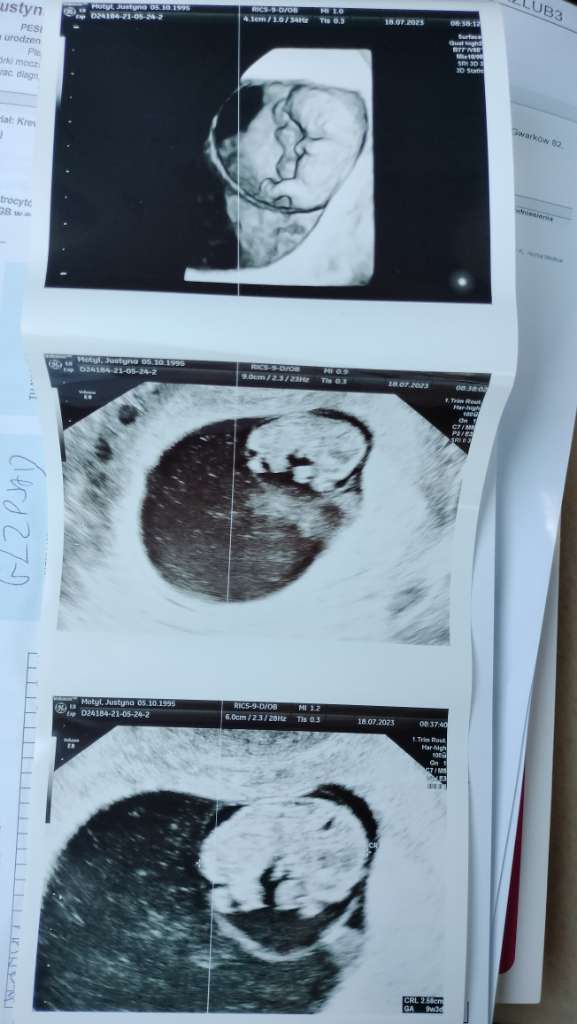

Hej pisze ponieważ wczoraj rano byłam na wizycie 9+3 wszystko okej . Wizyta była koło 9 rano. Koło 12 zobaczyłam czerwona kropkę na podpasce ale myślałam że to po goleniu bo więcej się nie pojawiło .

Podejrzewam to po badaniu USG mam nadzerke . Miałam plamienia na początku ciąży biore duphaston 3x1 objawy ciążowe mam . Czekam na wiadomość od lekarza napisałam do niego .